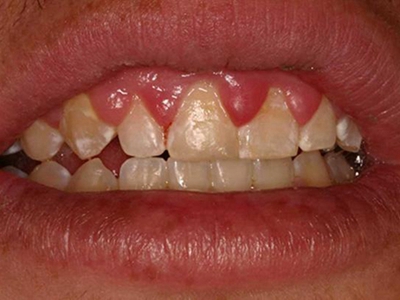

牙龈炎是发生于牙龈组织的炎症,患者可出现牙龈出血伴肿胀、发红、正常形态改变和偶尔不适等症状。本病主要由口腔卫生状况差导致,包括口腔不洁、牙菌斑等,诊断依据临床检查,治疗包括专业牙齿清洁和加强家庭口腔卫生。

牙龈炎可先引起牙齿与牙龈之间的沟(龈沟)加深,然后牙龈充血,炎症围绕一个或多个牙齿,伴牙龈乳头肿胀和易出血。一般无痛,可自行消退,也可维持轻度炎症数年。